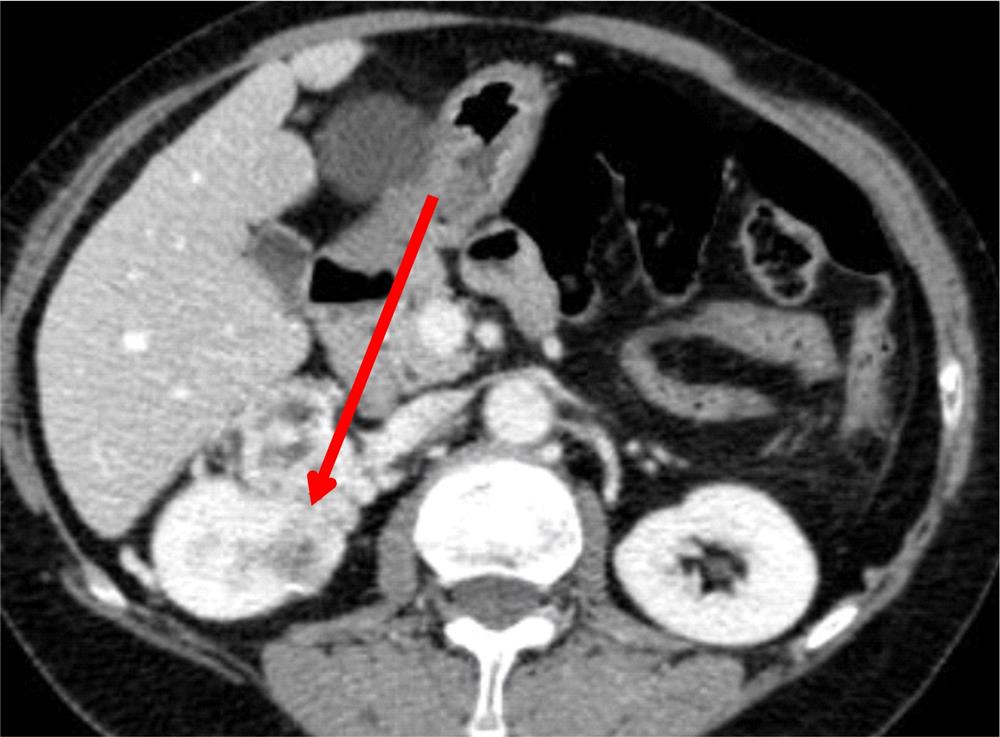

Рак Почки Фото